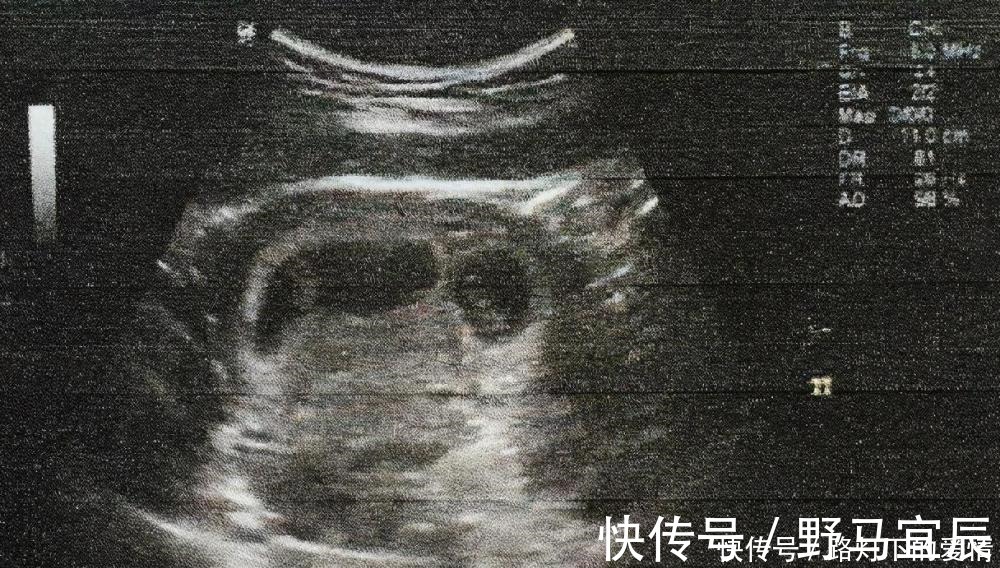

怀孕5-6周的孕妇已经可以通过B超检查看到胎囊,这就是最早的胚胎,还不是一个成型的胎儿。 在这个时间段能够看到胚胎长出了胎芽,同时胎心管也有轻微的跳动,这说明胎儿已经有心跳的表现。 如果出现胎心、胎芽并且情况正常,说明胎儿的发育良好。 但有的孕妇在有正常的胎心后还是会发生胎停,所以,即便是出现胎心,仍然不敢掉以轻心。至少要等到孕后12周也就是3个月后,情况才会稳定下来。